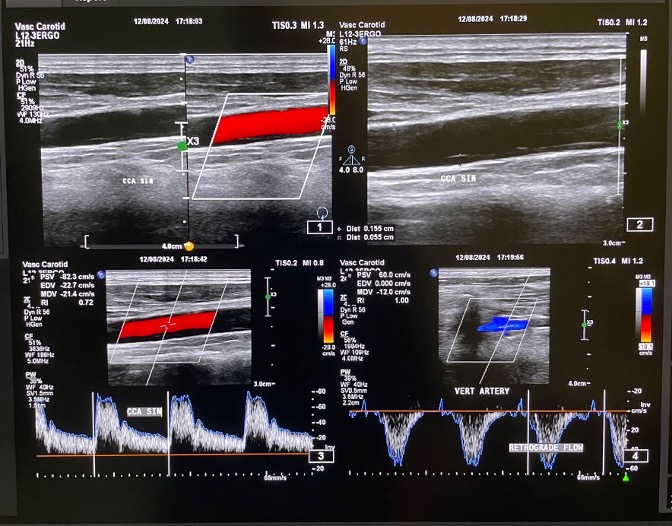

Relevant Test Results Prior to Catheterization

Duplex ultrasonography showed monophasic waveform in the left axillary, brachial, radial, and ulnar arteries. Retrograde flow was observed at the left vertebral artery, findings consistent with left subclavian steal syndrome. Computed Tomography Angiography (CTA) showed non calcified plaque with total occlusion from ostial left subclavian artery up to just before the origin of vertebral artery, with a tapered distal segment, and approximately 25–26 mm in length.